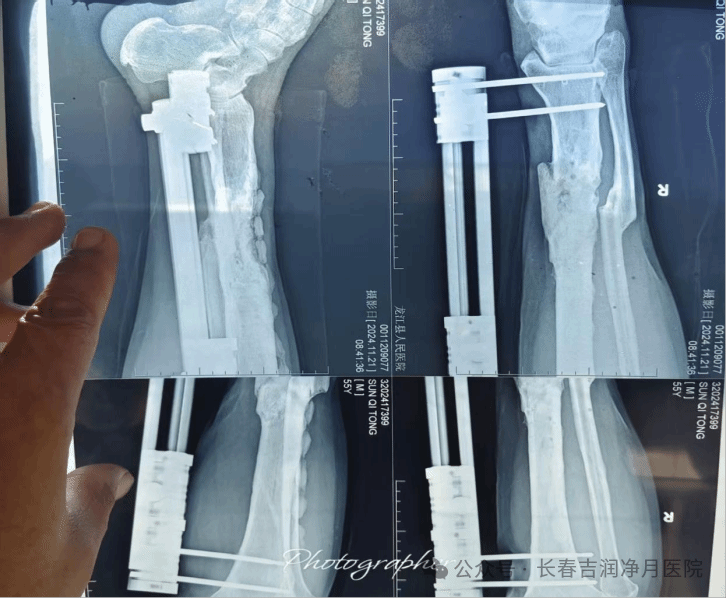

第一阶段(2021年):感染控制期。采用“清创+外固定+抗生素链珠”技术,通过局部持续高浓度抗生素释放,精准控制感染,为后续治疗创造条件。

(于铁成主任团队第一次术后两次复查片)